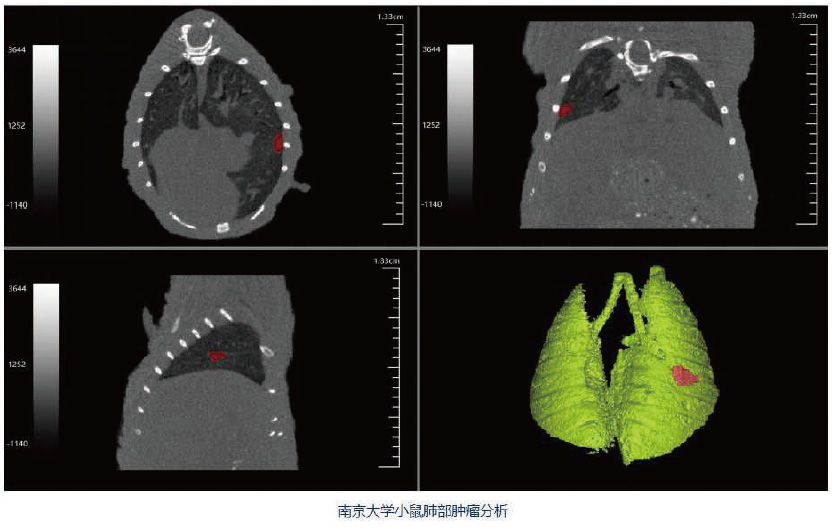

Hiscan VM Pro是一款快速灵活的活体显微CT,主要用于动物实验。其所用的锥束X射线可以看到样本的内部结构,最高分辨率可达18μm。可做小动物全身扫描,如小鼠、大鼠等。同时,可以扫描所选择的感兴趣区域,例如小鼠和大鼠的头部、脊椎、前肢 、后肢等。根据样本尺寸不同配以不同尺寸的扫描床,独特设计的扫描床可以防止小动物逃逸落进机器内。

广泛应用于骨骼疾病、肿瘤疾病、心血管疾病、炎症疾病、代谢疾病、免疫学、药效评价、生物材料等学科的临床前研究。